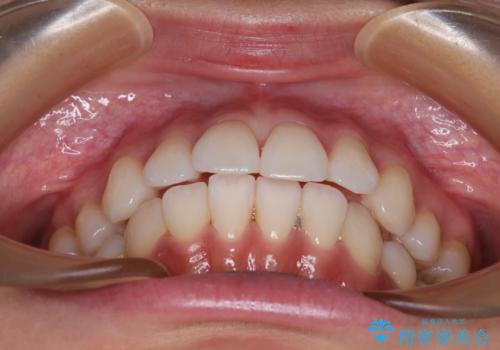

3. 抜歯矯正の軽度後戻りを解消 インビザライン矯正の治療後